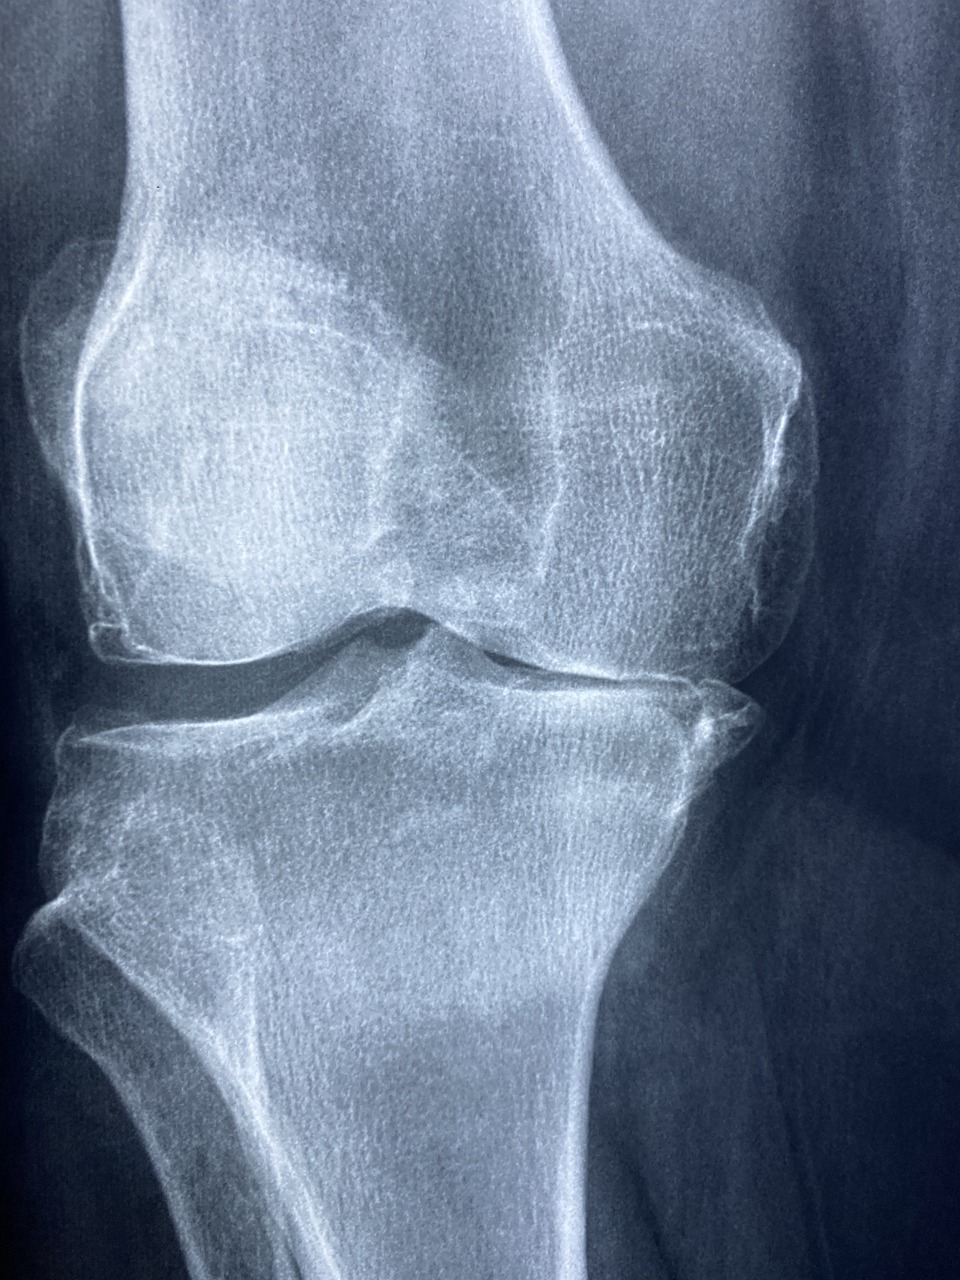

(1) 콘드로이친 효능- 관절건강

콘드로이친은 관절과 연골을 구성하고 있는 성분으로 철갑상어에 많이 들어있다고 합니다. 연골과 관절은 혈액의 움직임이 제한적이고 신경이 없어 손상 시의 회복이 제한적입니다. 콘드로이친은 관절과 연골의 구성성분 중 일부로 콘드로이친을 꾸준히 섭취한다면 연골조직 구성 단백질 생성을 촉진시켜 관절과 연골의 재생과 회복에 도움이 될 수 있습니다. 그렇게 되면 보행능력도 좋아져 잘 걸어 다닐 수 있습니다.

콘드로이친은 체내 염증수치를 감소시키는 효능이 있습니다. 특히 관절염에 효과가 좋다고 합니다. 관절과 연골의 구성성분이 관절과 연골을 강화해 줄 뿐만 아니라 염증도 해소해 주어 '관절엔 콘드로이친'이라는 문구가 생기게 되었습니다. 관절염 환자를 대상으로 한 연구에서 콘드로이친을 6개월 동안 섭취한 결과 전반적인 통증이 감소했다고 합니다.